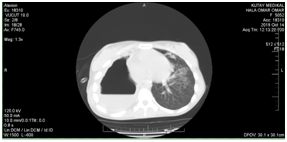

Female Patient (PT) 15 years old, referred to our hospital after more than 6 months of recurrent infections in right lower lobe (RLL) of the lung Figure A1 & A2. The PT had investigated, CXR was done Figure A3. The sputum was negative for TB many times. Bronchoscopy was done, no foreign body, no tumor, no anomalies, the washing was tested for TB and was negative. The decision for surgery was taken, the RLL was contracted, nodular and solid. RL Lobectomy was done. At second day post operation the PT had fever, sweat, no appetite and bad general condition. CXR revealed bilateral diffuse infiltrations. Figure B1. We decided to give her a trial TB treatment. After five days PT began to respond clinically. So TB treatment for minimum 6months is ordered.

• Follow up after one month; the PT has a very good general condition, chest CT revealed that the previous residual cavity has fulfilled with the omentum except a small a dead space Figure E1.